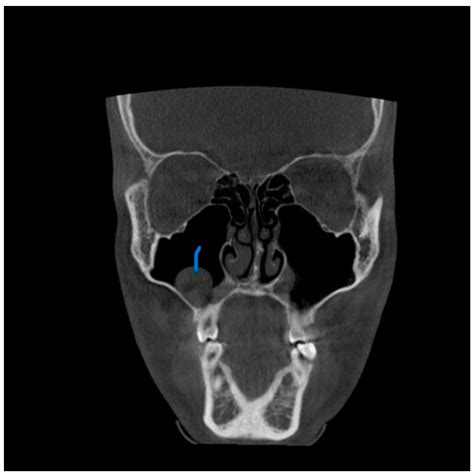

A Mxailliary Sinus CT scan, or Computed Tomography scan, is a non-invasive imaging procedure that uses X-rays to create detailed cross-sectional images of the sinuses. These images help doctors to identify abnormalities, infections, or structural issues within the sinuses. The scan is particularly useful for diagnosing conditions such as sinusitis, nasal polyps, and tumors.

The Mxailliary Sinus CT scan works by taking multiple X-ray images from different angles around the body. These images are then processed by a computer to create cross-sectional views of the sinuses. The resulting images provide a detailed view of the sinus cavities, allowing doctors to identify any abnormalities.

The results of a Mxailliary Sinus CT scan are interpreted by a radiologist, who will look for signs of:

• Inflammation: Swelling or infection in the sinuses.

• Obstruction: Blockages in the sinus passages.

• Abnormal Growths: Polyps, tumors, or other growths.

• Structural Issues: Deviated septum or other structural abnormalities.

Common Findings in a Mxailliary Sinus CT Scan

Some common findings in a Mxailliary Sinus CT scan include:

• Sinusitis: Inflammation of the sinuses, often due to infection.

• Nasal Polyps: Benign growths in the nasal passages.

• Tumors: Abnormal growths that may be benign or malignant.

• Fractures: Bone fractures in the sinus area, often due to trauma.

• Deviated Septum: A misaligned nasal septum that can cause obstruction.